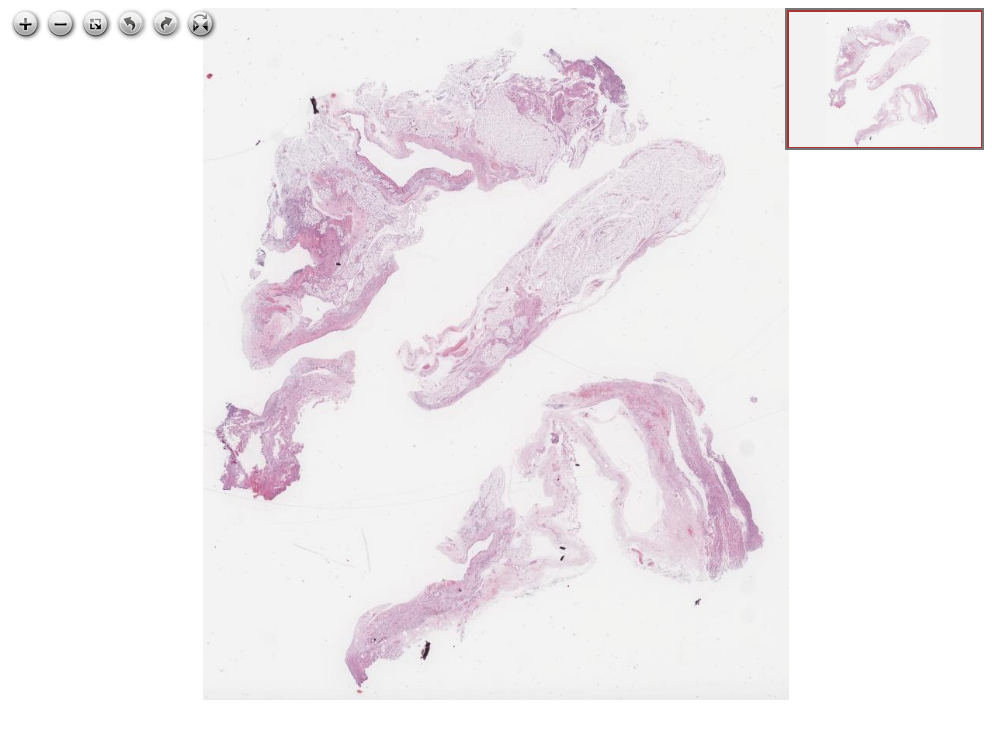

67.1 BS1 anjiosarkom, dalak, karaciğer

Mikroskopik görüntüleri inceleyin:

anjiosarkom, dalak, karaciğer